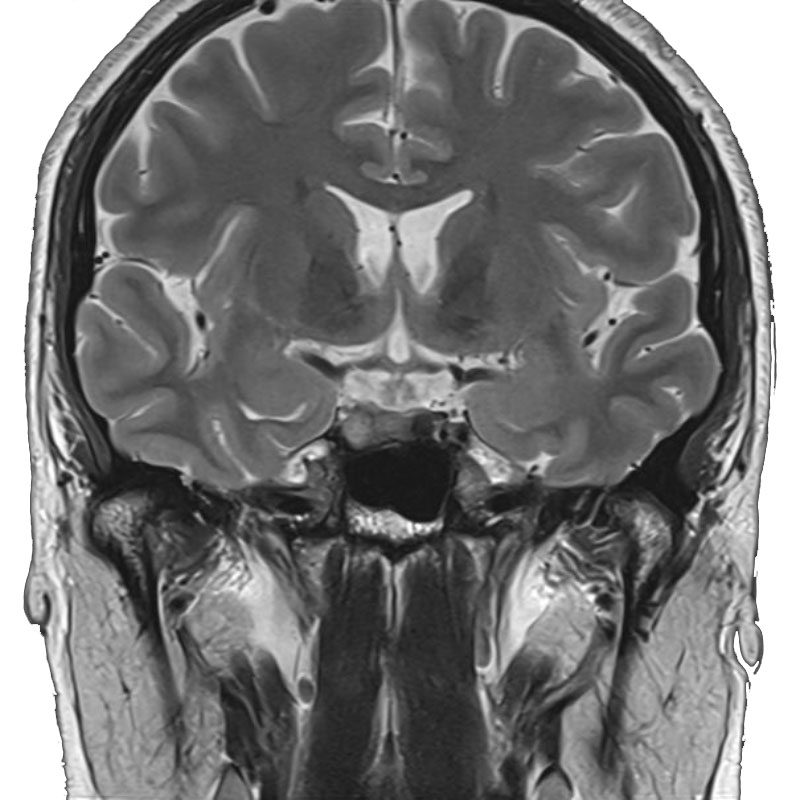

開頭症例

画像